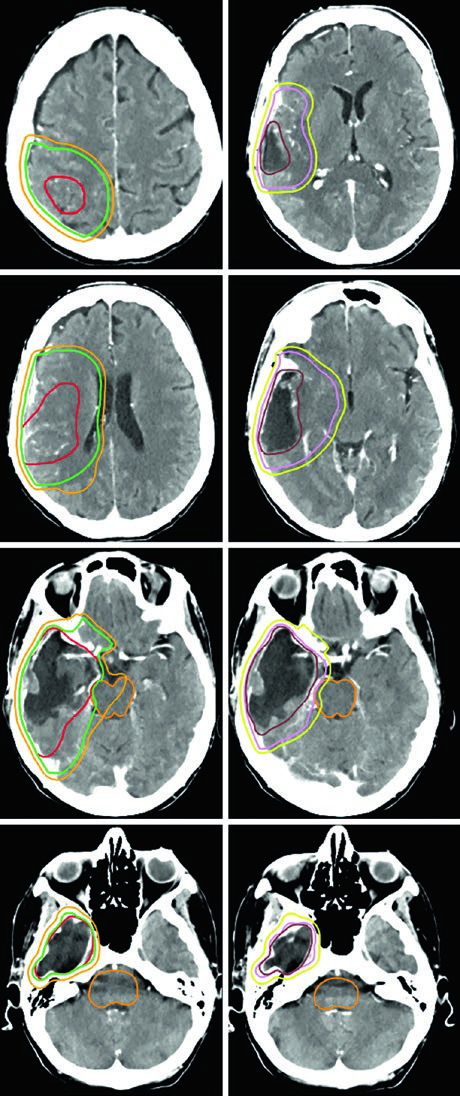

A dose padrão para gliomas de alto grau é de 59,4–60 Gy com fracionamento convencional. Para pacientes idosos, frágeis ou com performance status limitado, esquemas hipofracionados são uma alternativa validada: 40,05 Gy em 15 frações ou até 25 Gy em 5 frações, com margens reduzidas (0,5–1 cm). A tabela a seguir resume os volumes recomendados por tipo tumoral.

| Glioma anaplásico (captante) | Cone-down sequencial: PTV1 50,4 Gy (1,8 Gy/fx), PTV2 59,4 Gy (1,8 Gy/fx); ou SIB: PTV1 54,45 Gy (1,65 Gy/fx), PTV2 59,4 Gy (1,8 Gy/fx) | GTV1: volume T2/FLAIR; GTV2: cavidade pós-operatória + tumor residual na T1 pós-contraste | CTV1: 1,5 cm restrito anatomicamente; CTV2: 1,0 cm restrito | 0,3–0,5 cm |

| Glioblastoma | Cone-down: PTV1 46 Gy (2 Gy/fx), PTV2 60 Gy (2 Gy/fx); ou SIB: PTV1 50–51 Gy (1,67–1,7 Gy/fx), PTV2 60 Gy (2 Gy/fx) | GTV1: volume T2/FLAIR; GTV2: cavidade + tumor residual na T1 pós-contraste | CTV1: 2 cm restrito anatomicamente; CTV2: 2 cm restrito | 0,3–0,5 cm |

Um ponto prático fundamental: as expansões anatomicamente restritas significam que o CTV não cruza a linha média, não invade a cisterna pré-pontina, não se estende pelo crânio e não ultrapassa o tentório para a fossa posterior. No entanto, tratos em risco para disseminação tumoral contralateral — como o joelho do corpo caloso — devem ser incluídos. Essa nuance aparece claramente nos casos de glioblastoma frontal em que o tumor se aproxima do corpo caloso.

Pacientes idosos ou com performance status comprometido representam um desafio particular. O esquema de 40 Gy em 15 frações funciona bem quando há pouco volume FLAIR fora do tumor captante — o GTV inclui cavidade de ressecção, tumor residual e nódulos satélites na T1 pós-contraste, com expansão de CTV de apenas 1,0 cm e restrição anatômica ao tentório.

Para situações ainda mais agressivas em termos de prognóstico, o regime ultra-hipofracionado de 25 Gy em 5 frações é uma opção, com margens de 0,5 cm do GTV para o CTV. Um exemplo típico é o glioblastoma cerebelar — a cóclea e o tronco encefálico ficam visíveis e servem como referência direta na dosimetria.